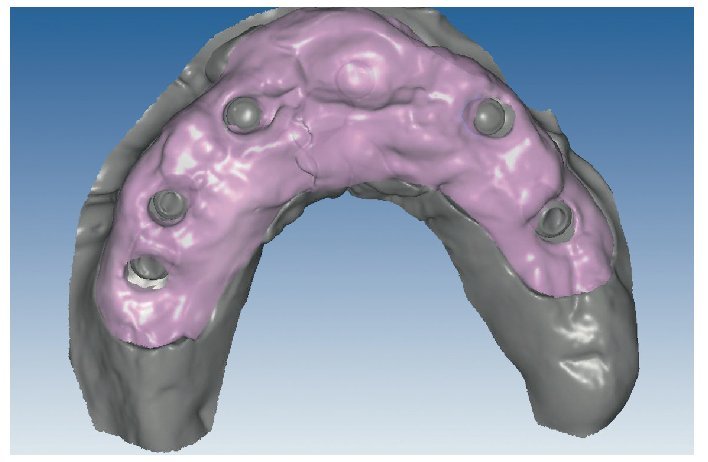

Mediante el uso de un escáner óptico de luz estructurada, los protocolos CAD registran los primeros datos relativos al modelo maestro con las correspondientes posiciones de implante (figs. 87 y 92). En el siguiente paso tiene lugar la digitalización de la planificación, previamente realizada en cera de escaneo matificada, de la restauración definitiva (figs. 88, 90 y 93). La subsiguiente conciliación de los datos mediante el uso del software de diseño dental permite al protésico planificar virtualmente el resto del procedimiento (figs. 89 y 91, 94 a 96) a partir del diseño de las estructuras (figs. 97 y 98).

Fig. 87. Imagen CAD del modelo maestro superior.

Fig. 90. La posición de los implantes en relación con la planificación.